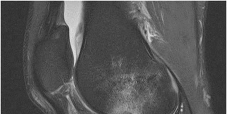

A 65-year-old male presents with worsening hand clumsiness and gait instability. Physical examination reveals a positive Hoffmann sign bilaterally and hyperreflexia in the lower extremities. Which of the following is the most sensitive imaging modality to evaluate the exact extent of the likely underlying pathology?

Correct Answer: Magnetic resonance imaging (MRI) of the cervical spine

Explanation:

The patient's symptoms (hand clumsiness, gait instability) and signs (Hoffmann sign, hyperreflexia) are classic for cervical spondylotic myelopathy (CSM), an upper motor neuron lesion caused by spinal cord compression. MRI of the cervical spine is the gold standard and most sensitive imaging modality to evaluate soft tissue structures, the intervertebral discs, and the degree of spinal cord compression or intrinsic cord signal changes (myelomalacia).